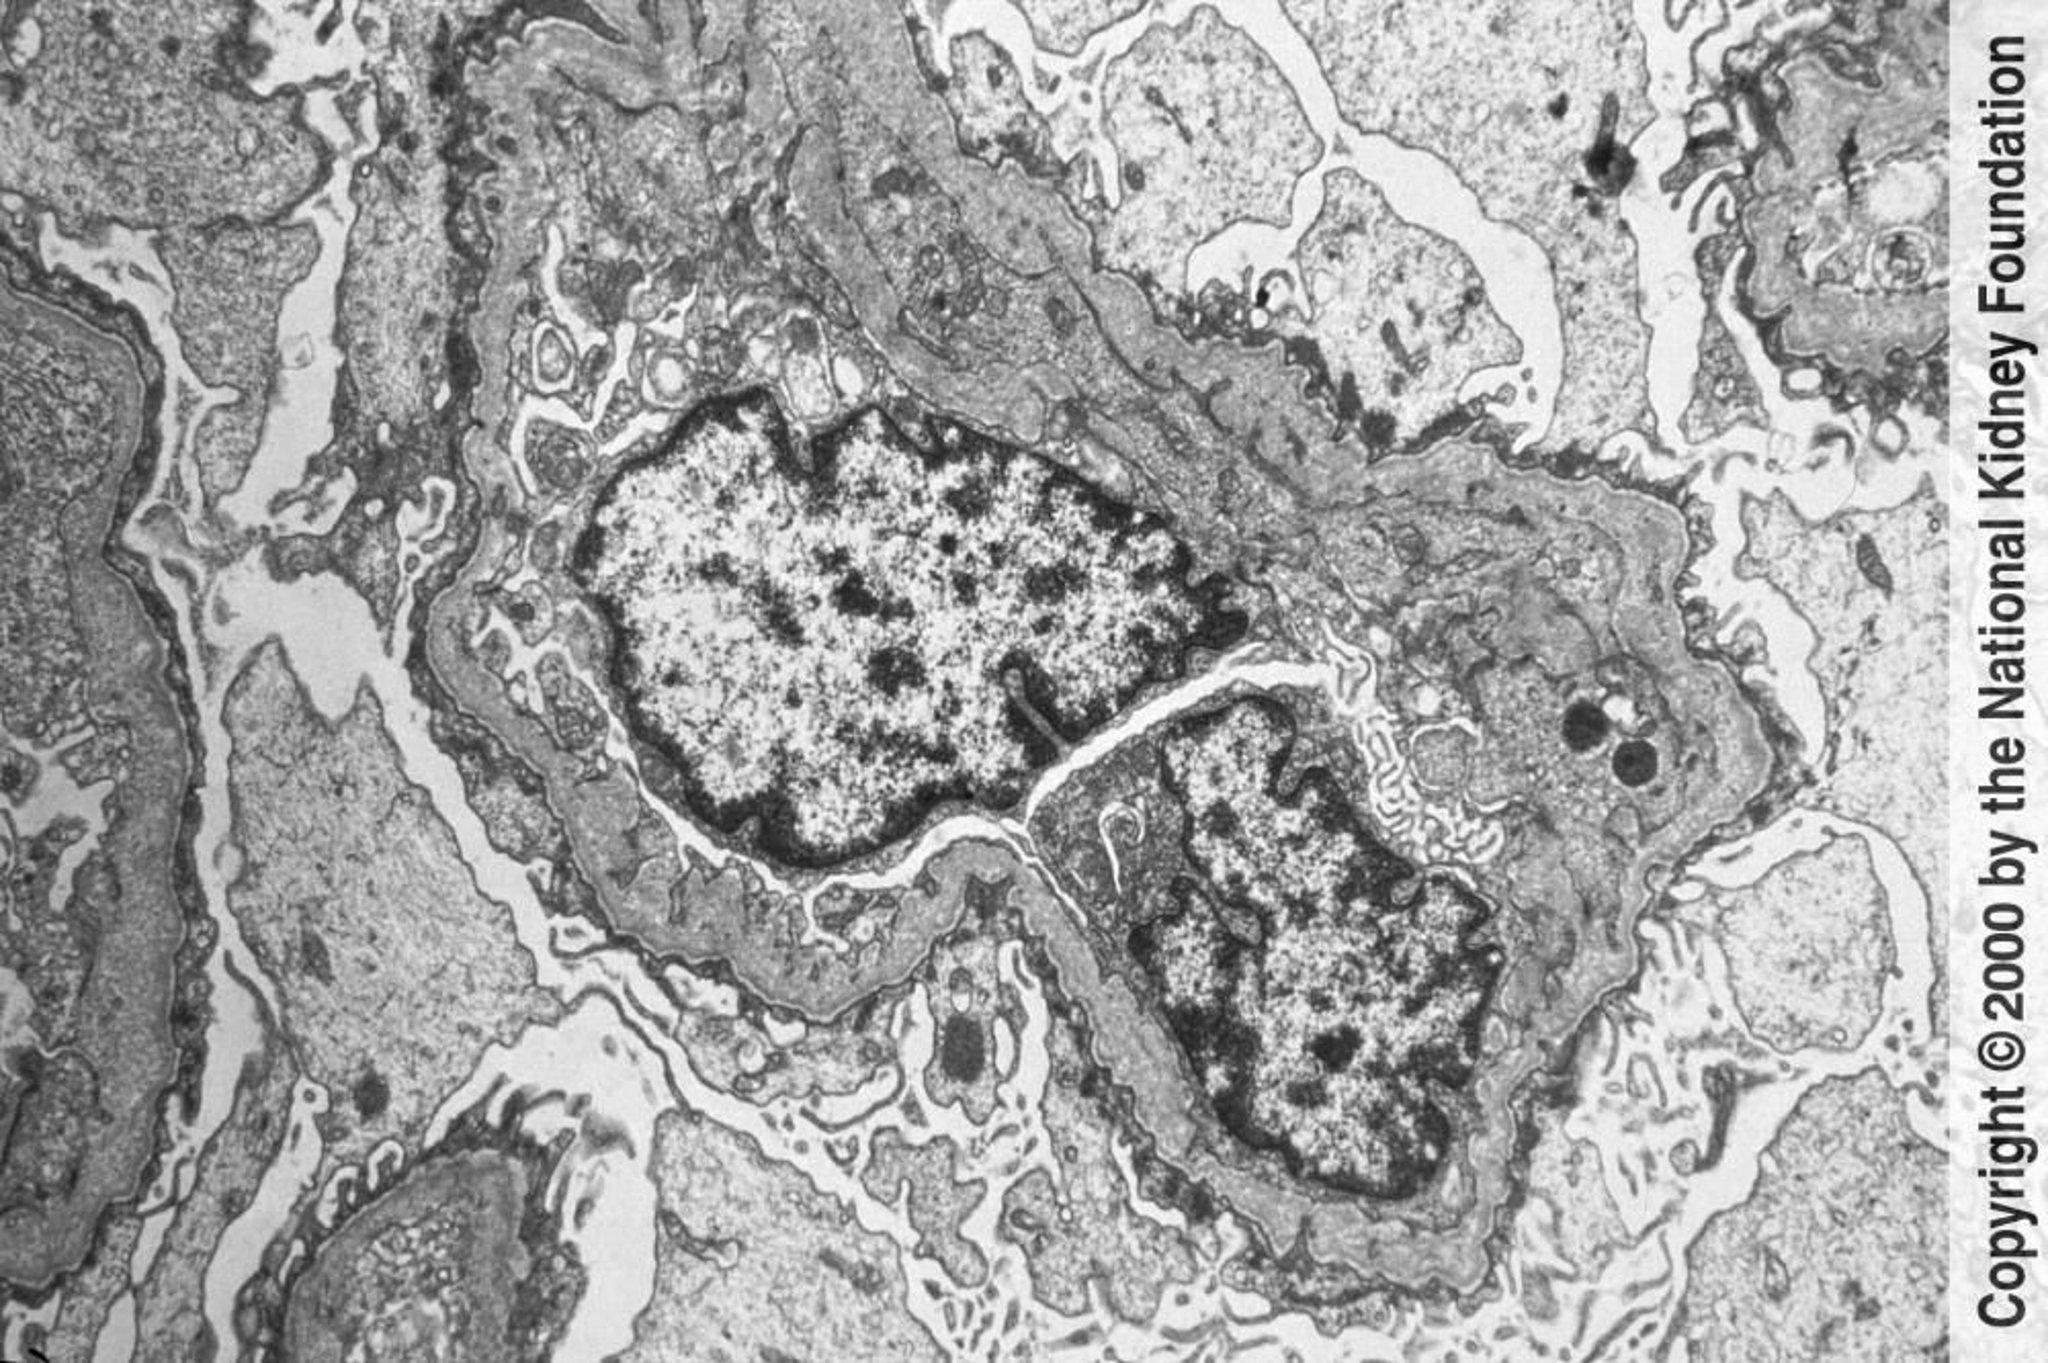

Le membrane basali glomerulari in la microscopia elettronica a trasmissione mostrano assottigliamenti e ispessimenti irregolari con aspetto a trama di cesto. I cambiamenti sono causati dai danni e dal rimodellamento (×6000).

Imagine fornita da Agnes Fogo, MD, and the American Journal of Kidney Diseases' Atlas of Renal Pathology (vedi www.ajkd.org).

La sindrome di Alport è una sindrome nefritica causata da mutazioni nei geni COL4A3, COL4A4 e COL4A5 che codificano la catena alfa-5 del collagene di tipo IV e che si traducono in alterazioni dei filamenti di collagene di tipo IV. Il meccanismo con cui un'anomalia del collagene causa una malattia glomerulare è ignoto, ma si presume vi sia un'alterazione della struttura e della funzione; nella maggior parte delle famiglie sono presenti ispessimento e assottigliamento della membrana basale glomerulare e tubulare con multilaminazione della lamina densa a distribuzione focale o locale (pattern a trama di cesto). L'evoluzione finale può portare a sclerosi glomerulare e fibrosi interstiziale.

Disorganizzazione caratteristica della lamina densa con incostante ispessimento e assottigliamento della membrana basale dei capillari glomerulari evidente alla microscopia elettronica